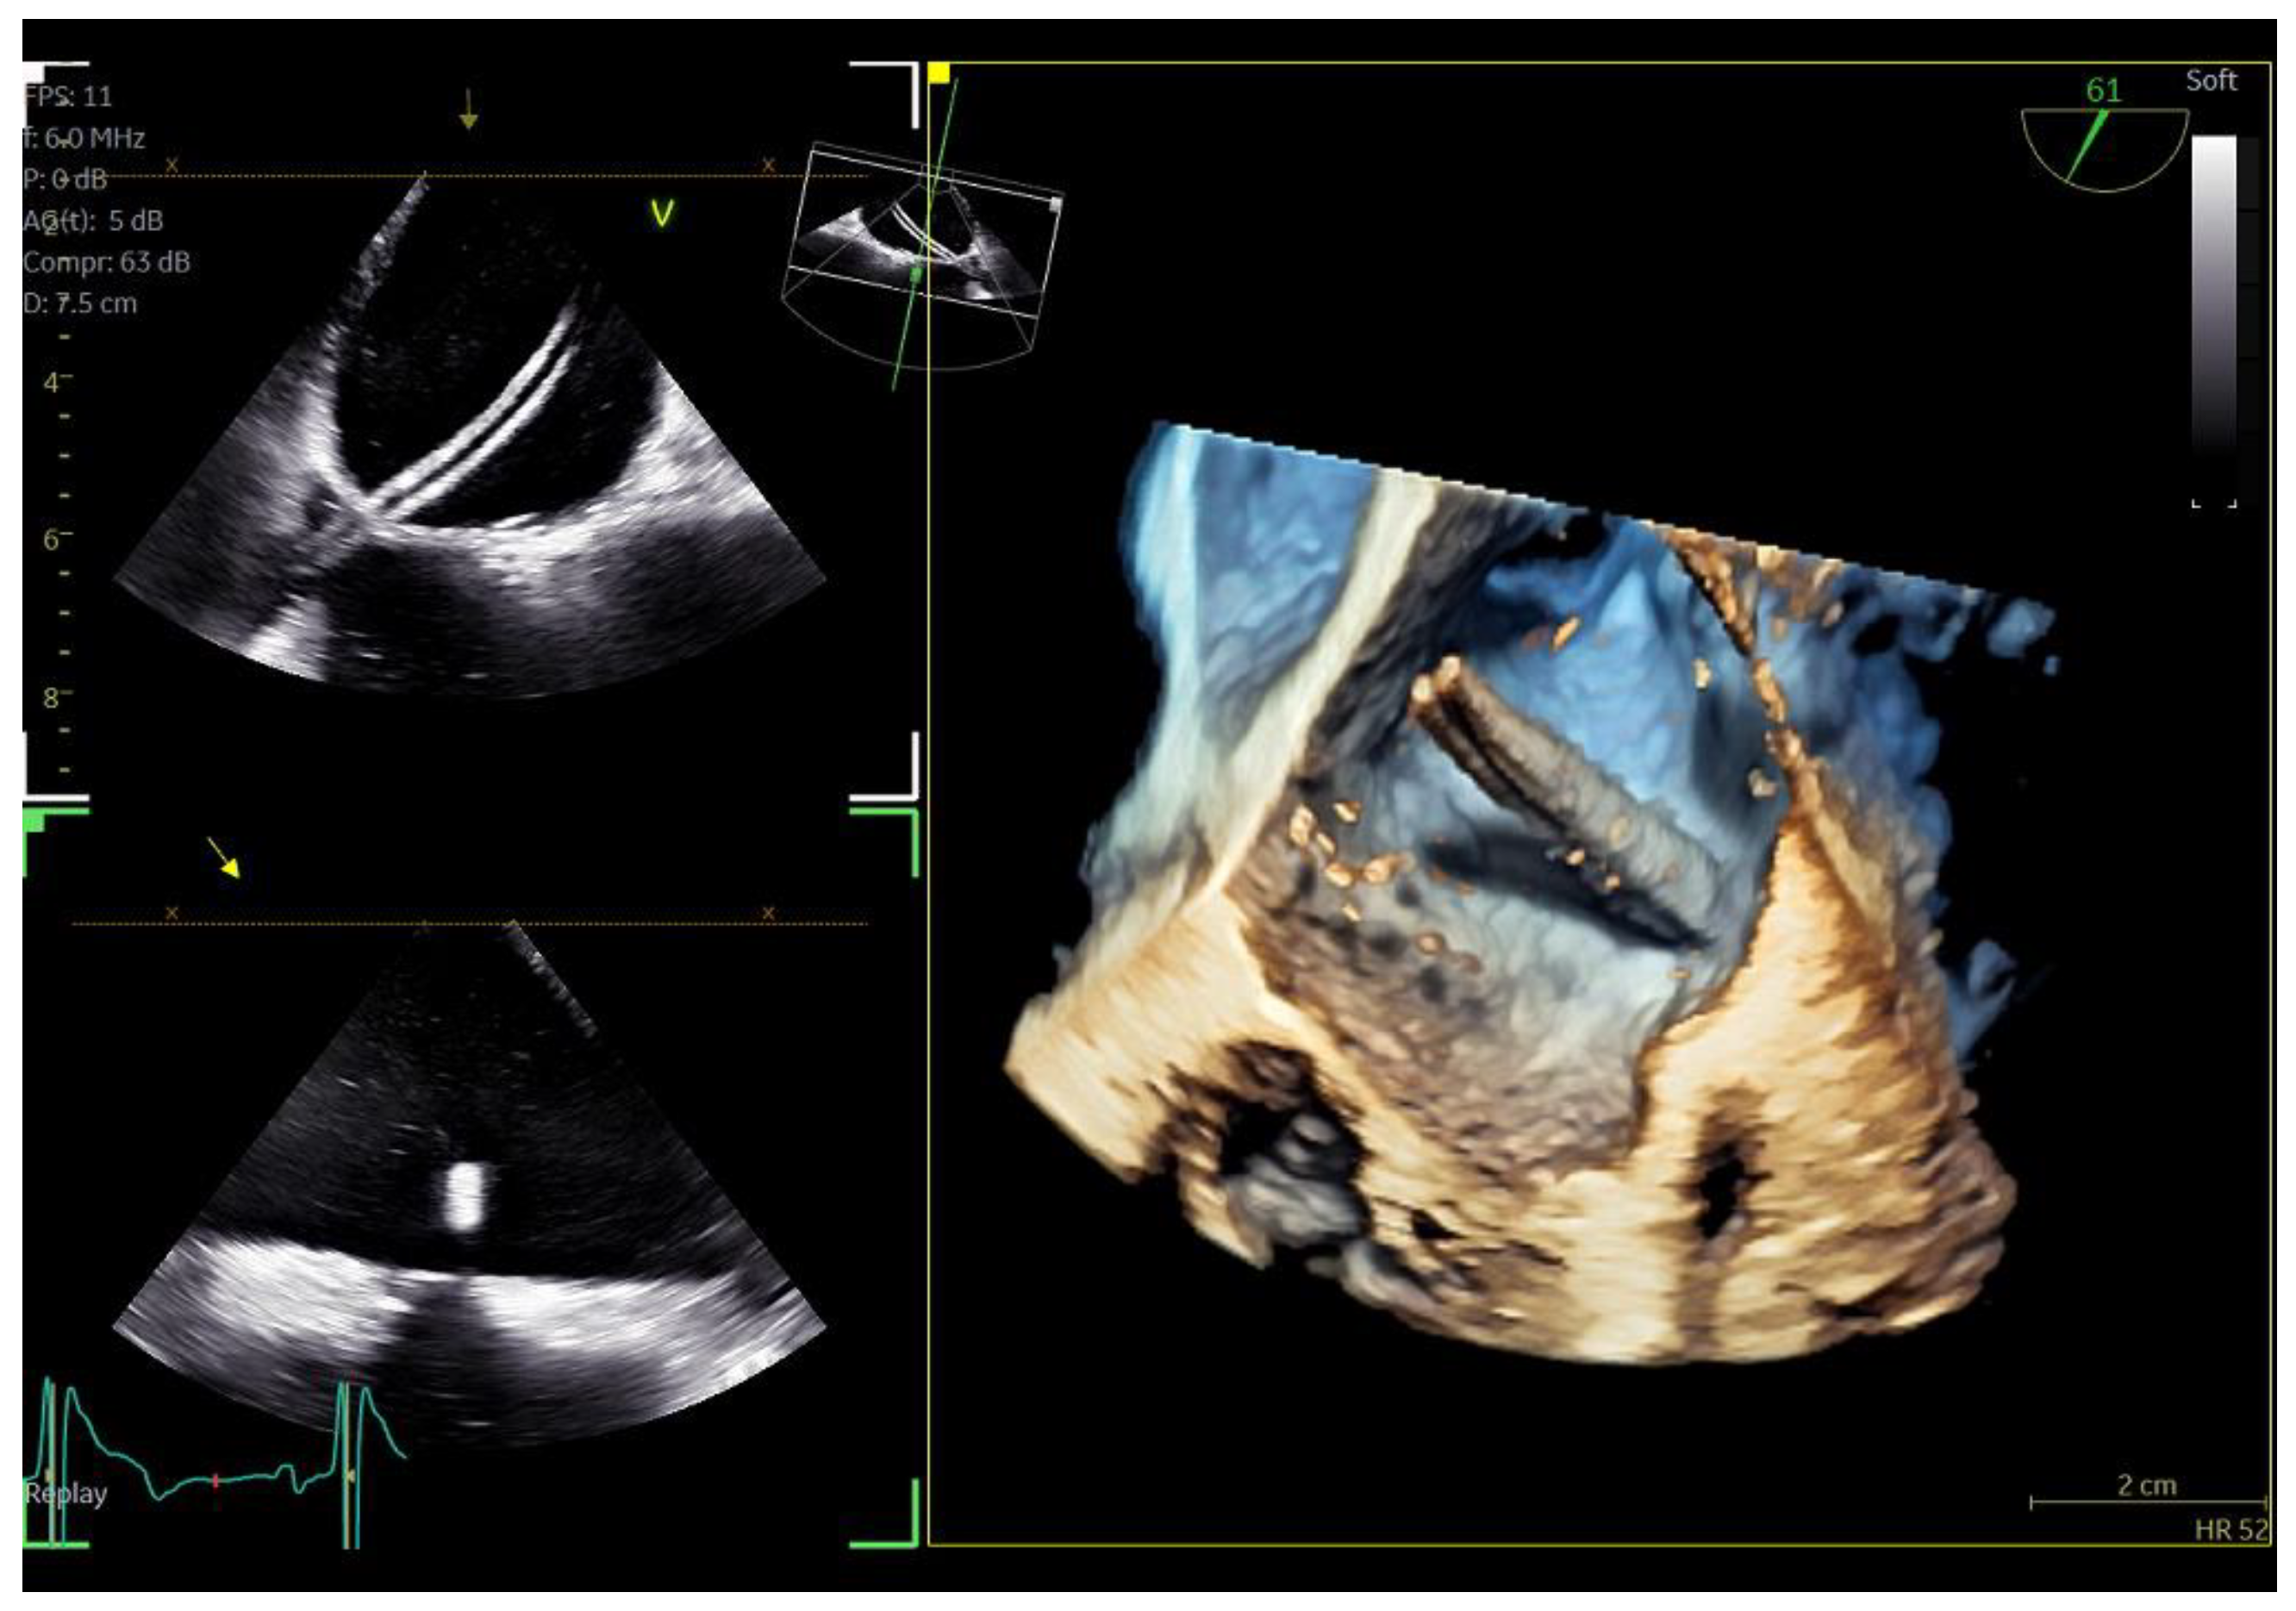

Figure 6.

Azimuth level (top left), elevation level (bottom left), and 3D volume-rendered image (right) of an SL0 catheter for the guidance of cryo-ablation procedure.

Figure 7.